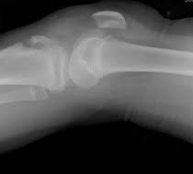

骨端の外傷性異常 ~ 骨端(線)の骨折-分離 ~ 骨端の裂離骨折 ~ 犬の裂離骨折

骨端の外傷性異常(traumatic disorders of the epiphysis) 骨端の損傷によっておこる疾患で、その主なものに骨端(線)の骨折-分離と骨端の裂離骨折があります。骨端(線)の骨折-分離(fracture-sepa...